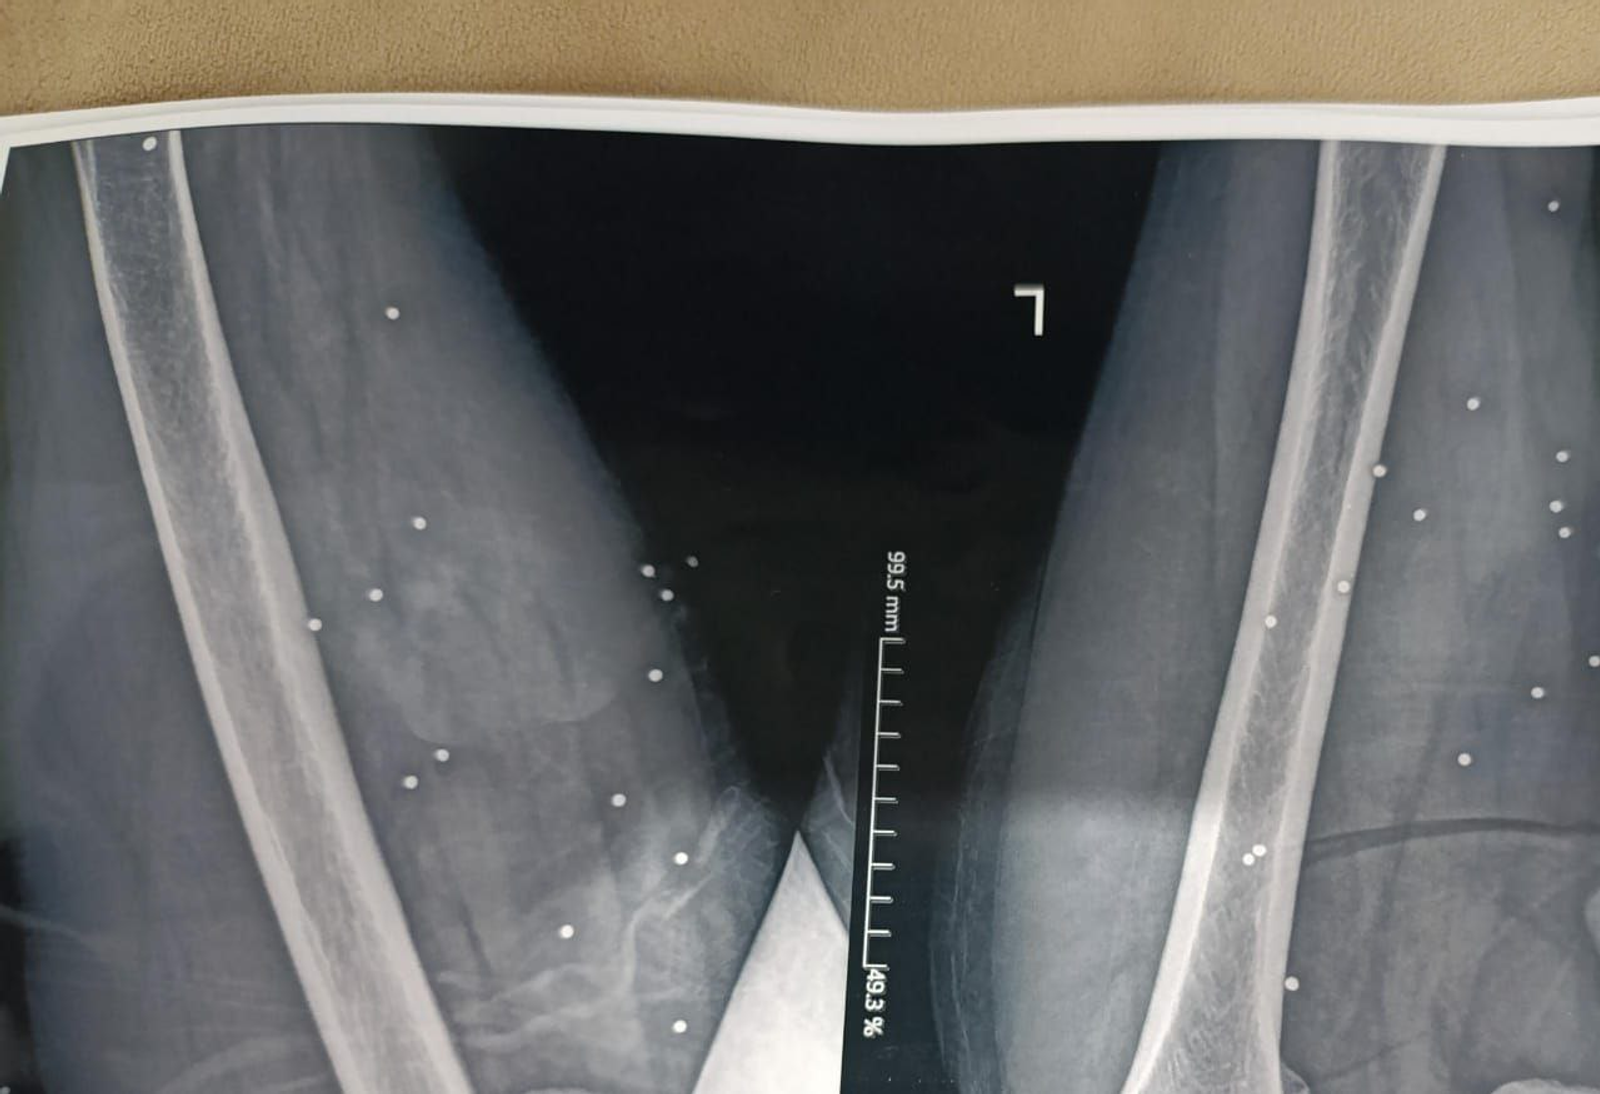

به گزارش روزنامه گاردین، بررسی ده‌ها تصویر پزشکی ثبت‌شده در جریان سرکوب اعتراضات در ایران نشان می‌دهد معترضان با ساچمه‌های فلزی و گلوله‌های کالیبر بالا هدف قرار گرفته‌اند. تصاویری که به گفته کارشناسان، از شدت جراحات و الگوی اصابت به نواحی حیاتی بدن حکایت دارند.

تصویر او یکی از بیش از ۷۵ مجموعه تصویر پزشکی شامل رادیولوژی و سی‌تی‌اسکن است که از یک بیمارستان در یکی از شهرهای بزرگ ایران به دست آمده و در اختیار گاردین قرار گرفته است. تصاویری که در طول یک شب و هم‌زمان با سرکوب اعتراضات دی‌ماه ثبت شده‌اند.

تصاویر، روایتی از شدت خشونت علیه معترضان و رهگذران ارائه می‌دهند.

ساچمه‌هایی که می‌توانند مرگبار باشند

ایران از معدود کشورهایی است که نیروهای امنیتی آن از ساچمه فلزی علیه شهروندان و برای سرکوب معترضان استفاده می‌کنند. هرچند هر ساچمه به‌اندازه گلوله جنگی قدرت تخریب ندارد، اما تعداد زیاد آن‌ها می‌تواند آسیب‌هایی بسیار شدید ایجاد کند.

در موارد دیگر، صدها ساچمه در بدن پراکنده شده و بافت نرم را تخریب کرده‌اند.

در پرونده «علی»، بیش از ۱۷۴ ساچمه در قفسه سینه راست دیده می‌شود. تراکمی که نشان می‌دهد شلیک از فاصله بسیار نزدیک انجام شده است. ریه راست او آسیب شدید دیده و تجمع خون و هوا در اطراف آن مشاهده می‌شود.

کارشناسان پزشکی گفته‌اند حتی با مداخله فوری، خطر مرگ در چنین شرایطی بالاست.

بر اساس این گزارش، دست‌کم ۹ بیمار از ناحیه لگن یا اندام تناسلی هدف قرار گرفته‌اند؛ برخی با ساچمه و برخی با گلوله‌های کالیبر بالا.

در یکی از تصاویر، نزدیک به ۲۰۰ ساچمه در ران و لگن یک زن میانسال دیده شده است.

تحلیل پزشکی نشان می‌دهد این نوع جراحات می‌تواند به آسیب شدید اندام‌های داخلی، بی‌اختیاری در کنترل ادرار، ناباروری و ناتوانی جنسی منجر شود.

این پیامدها در بسیاری از موارد، دائمی خواهند بود.